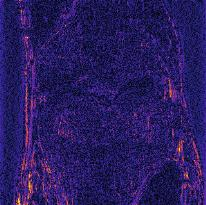

Recently, deep neural networks have greatly advanced undersampled Magnetic Resonance Image (MRI) reconstruction, wherein most studies follow the one-anatomy-one-network fashion, i.e., each expert network is trained and evaluated for a specific anatomy. Apart from inefficiency in training multiple independent models, such convention ignores the shared de-aliasing knowledge across various anatomies which can benefit each other. To explore the shared knowledge, one naive way is to combine all the data from various anatomies to train an all-round network. Unfortunately, despite the existence of the shared de-aliasing knowledge, we reveal that the exclusive knowledge across different anatomies can deteriorate specific reconstruction targets, yielding overall performance degradation. Observing this, in this study, we present a novel deep MRI reconstruction framework with both anatomy-shared and anatomy-specific parameterized learners, aiming to "seek common ground while reserving differences" across different anatomies.Particularly, the primary anatomy-shared learners are exposed to different anatomies to model flourishing shared knowledge, while the efficient anatomy-specific learners are trained with their target anatomy for exclusive knowledge. Four different implementations of anatomy-specific learners are presented and explored on the top of our framework in two MRI reconstruction networks. Comprehensive experiments on brain, knee and cardiac MRI datasets demonstrate that three of these learners are able to enhance reconstruction performance via multiple anatomy collaborative learning.